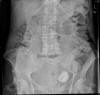

Fecalomas.